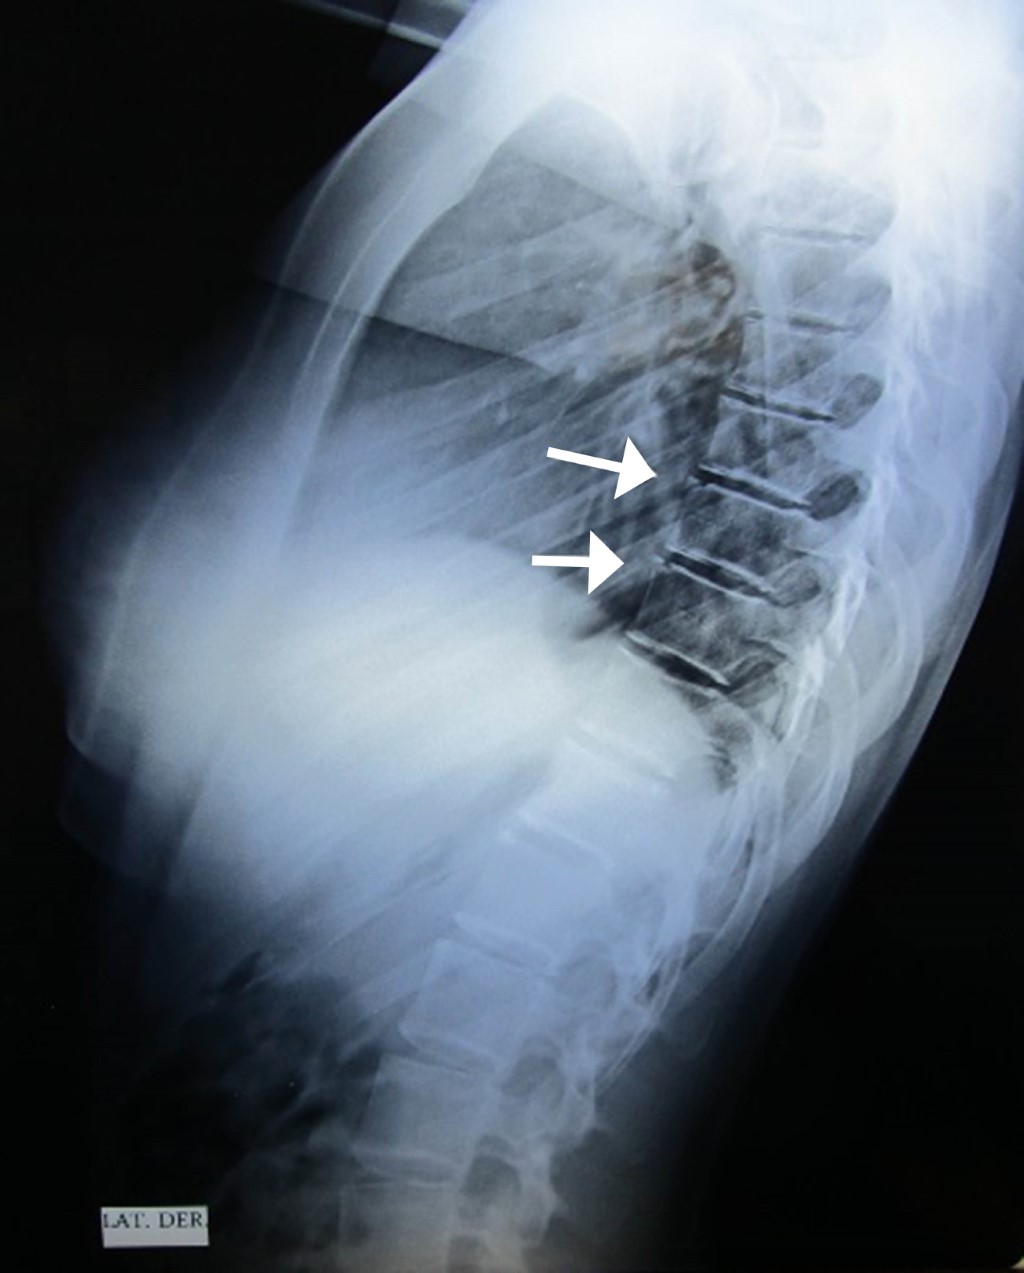

Femenino de 17 años que acude por defectos posturales. A la exploración se encontró cifosis dorsal e hiperlordosis lumbar, por otro lado asintomática, se solicitaron radiografías de columna encontrando como hallazgo incidental dos vértebras limbus.

El hueso limbus fue descrito por Schmorl en 1927, es un osículo adyacente en el borde anterior, habitualmente superior, de un cuerpo vertebral, (a la vértebra que lo presenta se le ha denominado vértebra limbus) pero pueden observarse con menor frecuencia en los márgenes anteroinferior o posteroinferior; representan una herniación intraósea del núcleo pulposo a través del anillo apofisario vertebral, antes de su fusión completa en el esqueleto inmaduro;1 habitualmente es asintomático y suele diagnosticarse como un encuentro radiológico incidental, se percibe con mayor frecuencia en la región lumbar, en donde se ha relacionado con lumbalgia mecánica en jóvenes,2 mientras que es menos común en las regiones cervical y dorsal. La radiografía lateral de columna es suficiente para el diagnóstico, se advierte un defecto óseo radiolúcido similar a una banda oblicua bien definida en el margen anterosuperior del cuerpo vertebral, que aísla un pequeño fragmento óseo triangular, de márgenes bien definidos, separado del cuerpo vertebral.3 El diagnóstico diferencial debe efectuarse con fractura límbica, espondilodiscitis, tumores vertebrales, hernias intraesponjosas de Schmorl, fractura en lágrima y hueso intercalar (Figuras 1 y 2).4

Figura 1

Figura 2